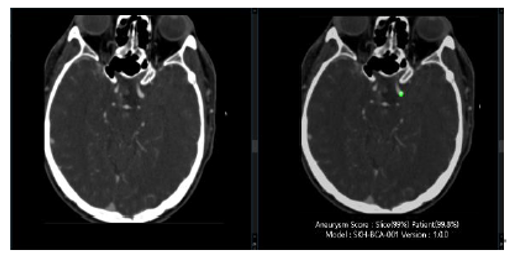

Worklist Prioritization

Urgent cases are automatically highlighted and sorted by severity.

Frees attention to the highest-risk cases first. Delivers AI-supported findings within seconds.

Detects and localizes unruptured cerebral aneurysms using deep learning. Marks aneurysm locations, outlines, and diameter ranges on CTA images.